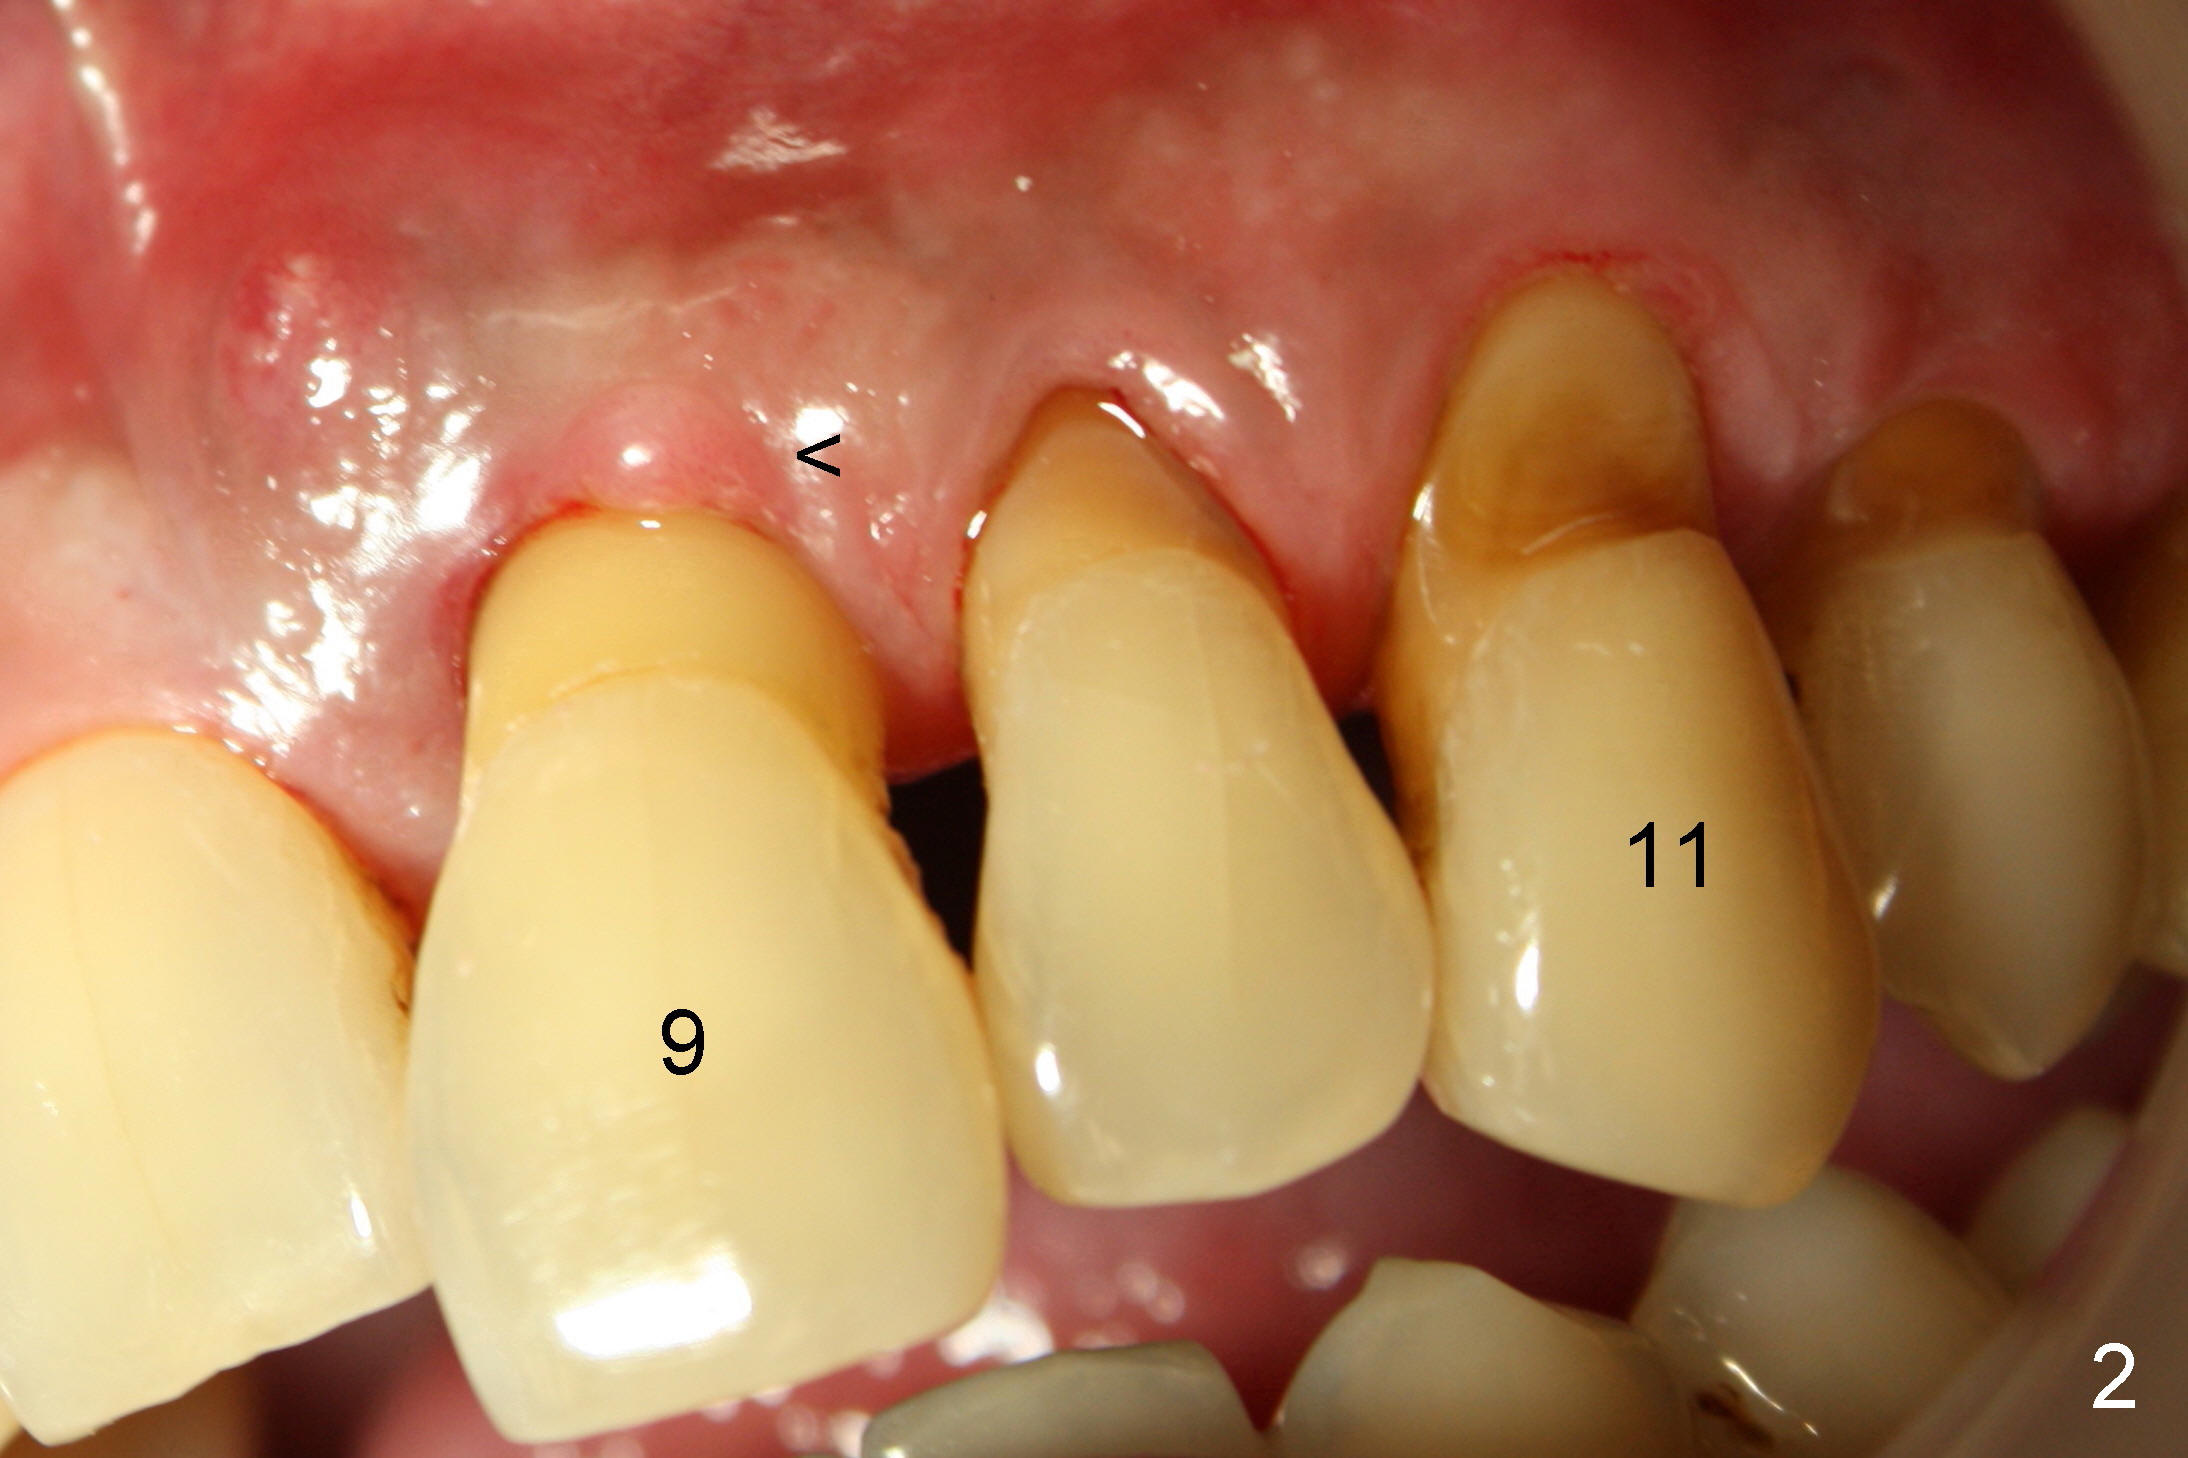

3. He has lost several upper teeth: #2,3,4,14 and 15.  The remaining teeth are loose, particularly #6,7, and 9 (Fig.1-4).  There are several treatment options for him.  Tell him that the doctor will discuss with him

5. First of all, #6,7 and 9 will be extracted with immediate implants and provisional

6. Since the tooth # 6 shifts the most (Fig.1 arrow), it will be extracted first (the reason will be further explained in section #9), followed by thorough curettage, copious irrigation and soak with antibiotic